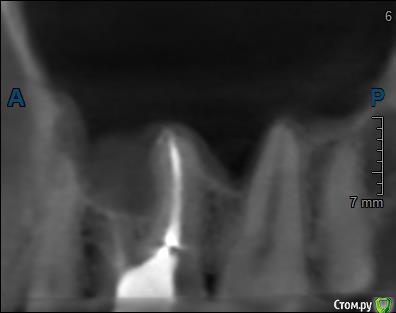

Здравствуйте! Верхний правый шестой зуб пломбировали 3 месяца назад. Примерно месяц назад он начал ныть, после насморка, сначала периодами, а теперь почти постоянно. При постукивание (ощущается не совсем так, как другие зубы) и пальпации десны он не болит. 2,5 месяца назад удаляли кисту из гайморовой пазухи. Может ли быть это какое-то воспаление и есть ли вероятность устранить его какими-нибудь антибиотиками, если да, то как, или может удалить зуб? Если есть воспаление, то какие могут быть последствия если не удалить зуб?

(Снимки с КТ, первые 8(Image) - сделаны сейчас,по 4 в разных проекциях, вторые 8(Before) - сделаны 5 месяцев назад до удаление кисты и повторного пломбирование зуба( до повторного пломбирование он реагировал на горячее, был запломбирован 3 года))

переличили зуб адекватно, во всяком случае по снимкам